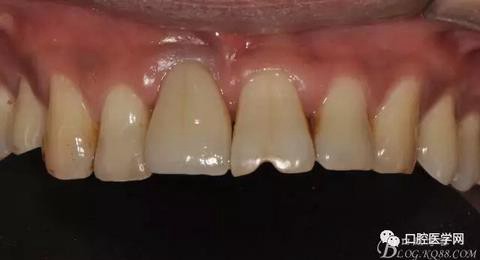

圖8 術(shù)后即刻臨時冠修復(fù)

圖9 三個月后袖口形成正位照